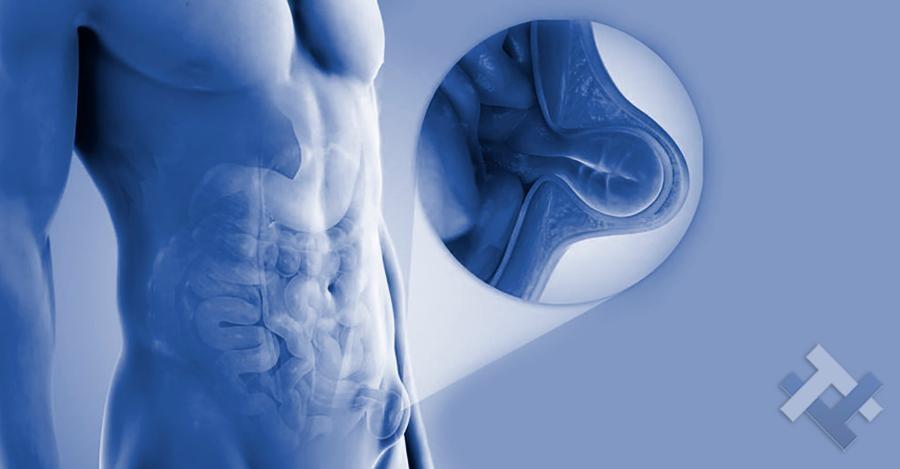

Κήλες - Κοιλιοκήλες

Ο Γενικός Χειρουργός Λιάγκος Γεώργιος MD PhD εκτελεί τις επεμβάσεις Λαπαροσκοπικά, Ενδοσκοπικά, Ανοιχτά Ελάχιστα Επεμβατικά και με Laser. Η θεραπεία εξατομικεύεται σε κάθε ασθενή ανάλογα με τις ανάγκες του. Αναλαμβάνει περιπτώσεις όπως κήλες και κοιλιοκήλες (αντιμετώπιση βουβωνοκήλης, αντιμετώπιση ομφαλοκήλης, θεραπεία επιγαστρικής κήλης, κήλη των αθλητών (Σύνδρομο κοιλιακών προσαγωγών), αντιμετώπιση μετεγχειρητικής κήλης, θεραπεία Μηροκήλης), πέτρες στη χοληδόχο κύστη, λαπαροσκοπική χολοκυστεκτομή, αντιμετώπιση Κύστη Κόκκυγος με λέιζερ (laser), παθήσεις πρωκτού, χειρουργική laser σύγχρονων κυκλικών ινών (αιμορροΐδες αντιμετώπιση, θεραπεία αιμορροϊδων με laser (LHP), αφαίρεση αιμορροΐδων με υπερήχους (HALL-RAR), χωρίς Χειρουργείο με ελαστικούς δακτυλίους (Τεχνική BARON-RBL), θεραπεία ραγάδας πρωκτού (Ραγάδα δακτυλίου), θεραπεία περιεδρικού συριγγίου, θεραπεία περιεδρικού αποστήματος, κονδυλώματα πρωκτού Θεραπεία, δερματικό ράκος (Skin tag) εκτομή, αντιμετώπιση Kνησμού, καρκίνος πρωκτού θεραπεία), παθήσεις Δέρματος, χειρουργική με laser CO2, αφαίρεση μορφωμάτων δέρματος - βιοψίες, αφαίρεση ελιάς (Σπίλου), σμηγματογόνος κύστης θεραπεία, αφαίρεση λιπώματος, είσφρυση όνυχος χειρουργείο, καρκίνος δέρματος θεραπεία, οξεία σκωληκοειδίτιδα, παθήσεις Λεπτού και Παχέος Εντέρου, ειλεός λεπτού εντέρου, εκκολπωμάτωση (Εκκολπωματίτιδα) σιγμοειδούς, καρκίνος παχέος εντέου, κολοστομίες, port χημειοθεραπείας κ.α. εξυπηρετώντας Παγκράτι και γύρω περιοχές.